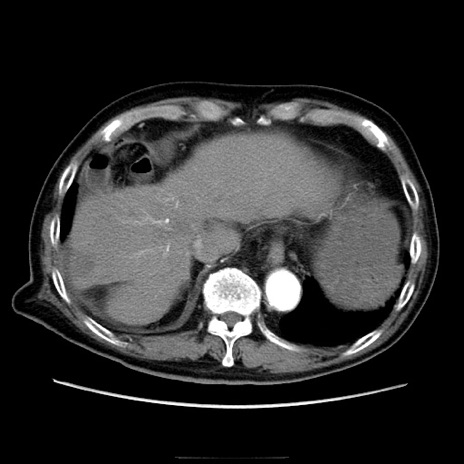

症例21(横断像)

【症例】70歳代男性

【現病歴】肝硬変・肝細胞癌にてかかりつけの方。約9時間前に食後より腹痛出現。症状が徐々に増悪し、嘔吐出現したため来院。

【既往歴】肝硬変、肝細胞癌(RFA、TACE後)

【身体所見】意識清明、表情苦悶様、BT 36℃、BP 129/78mmHg、P 88bpm、SpO2 97%(RA)、右上腹部から心窩部にかけて圧痛あり、反跳痛なし、筋性防御あり。

【データ】WBC 5800、CRP 0.16